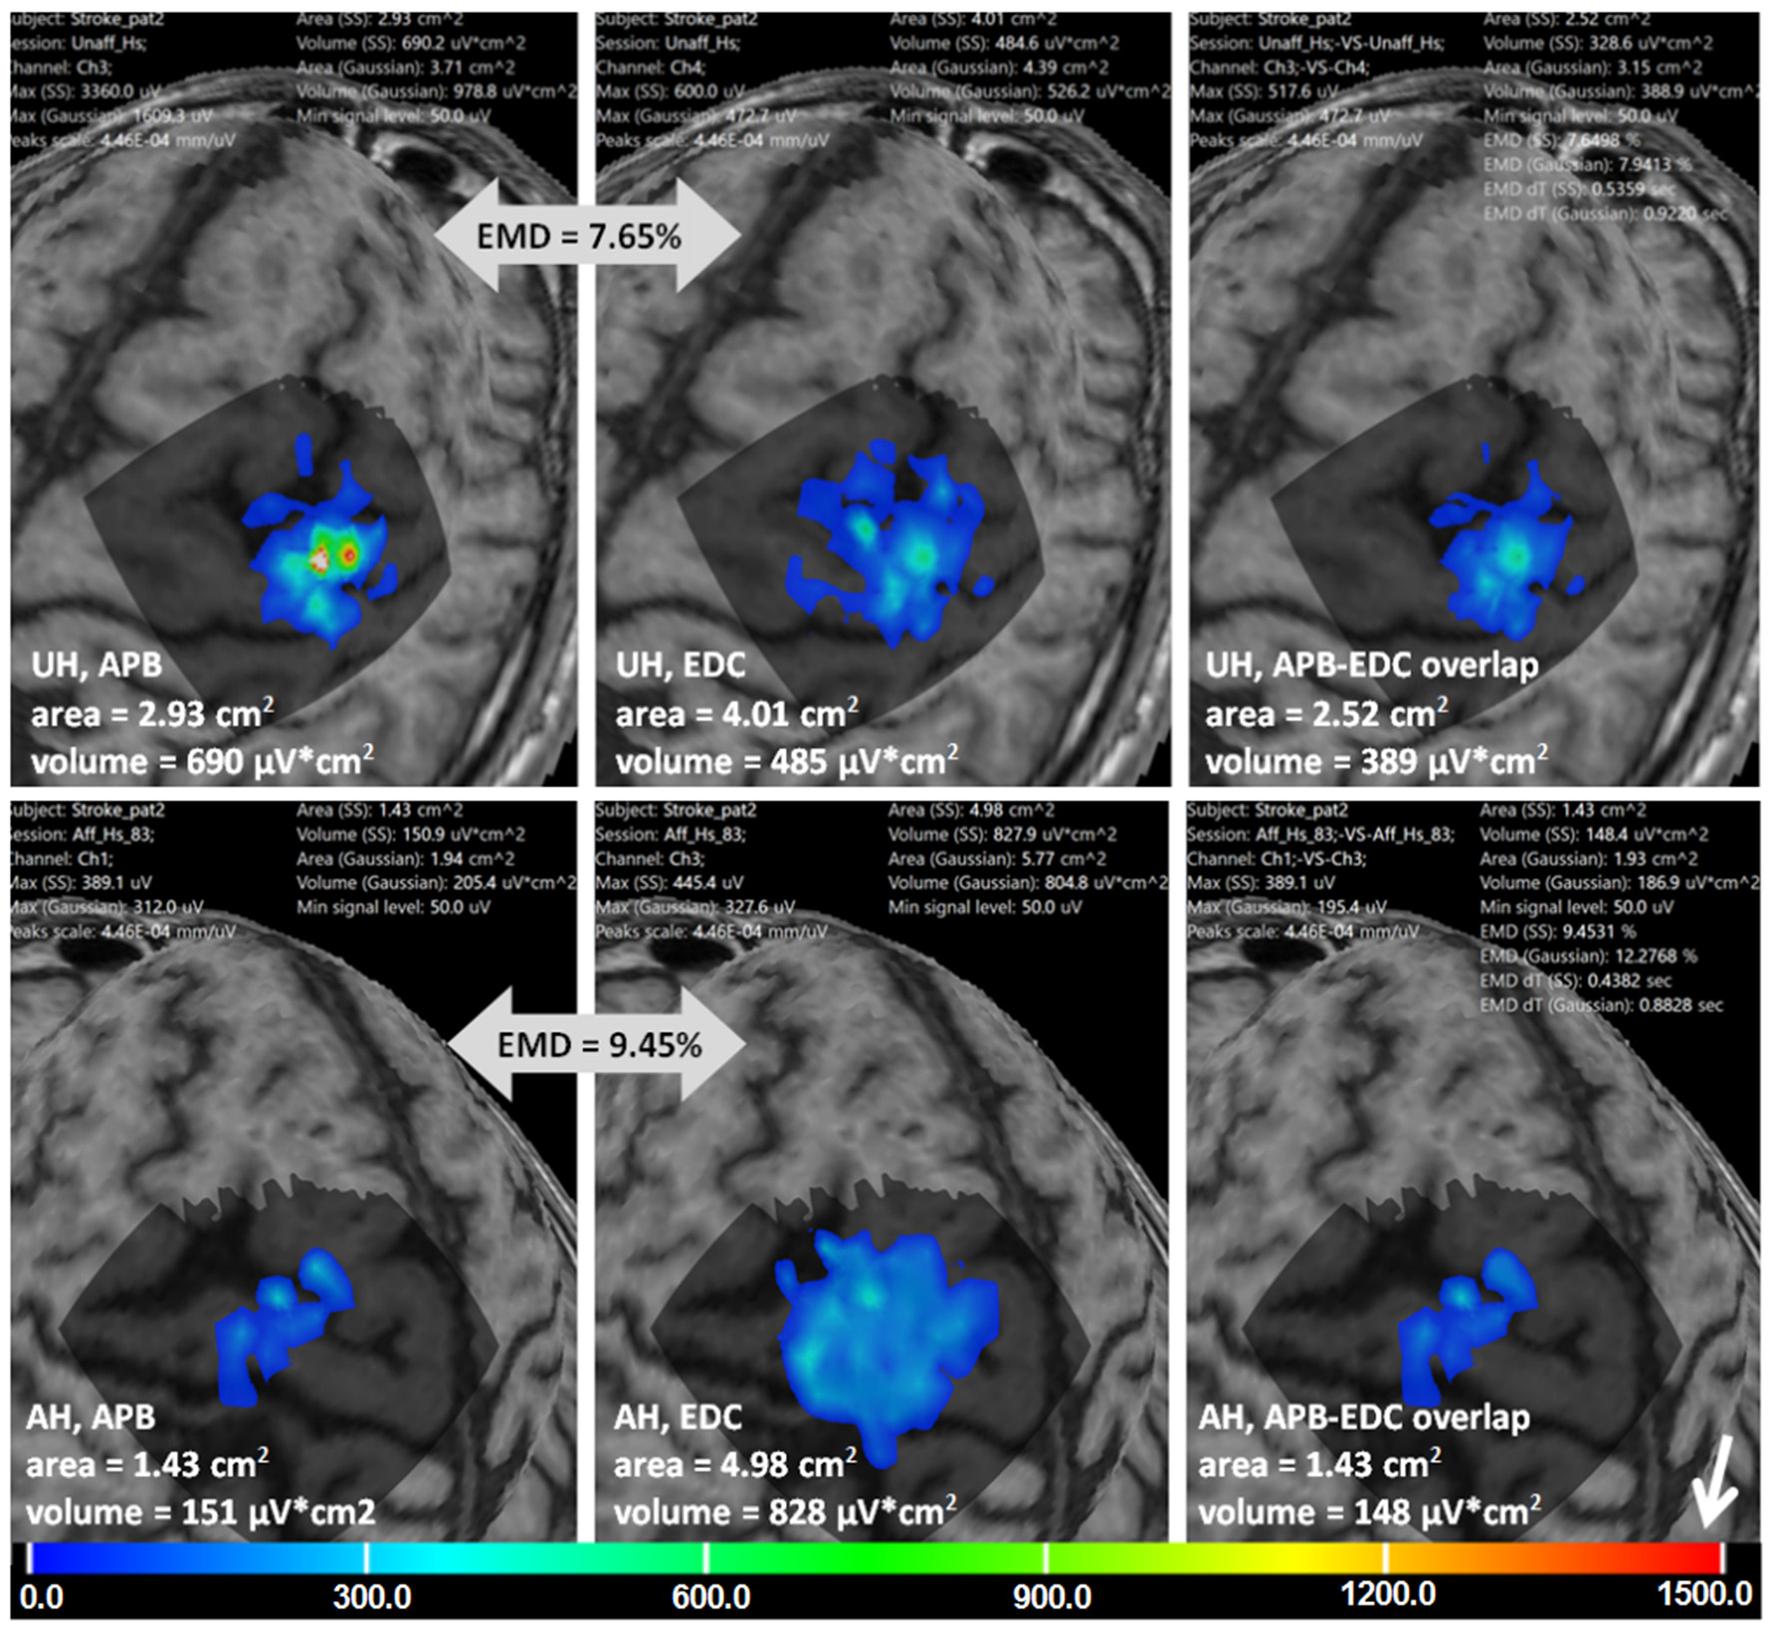

For the third example we used the data from a chronic stroke patient (male, 55 years old, 20 months after the incident) with the cortical-subcortical ischemic lesion in the left hemisphere and favorable upper limb motor recovery (55 by Fugl-Meyer upper extremity scale). The RMTs for APB was 51% for the unaffected hemisphere (UH) and 75% for the affected hemisphere (AH). A total amount of the points was 120 for the UH and 125 for the AH, each spot was stimulated only once.

Figure 8 is an example of multi-muscle TMS mapping in the ischemic stroke patient. A greater difference between APB and EDC representations in the AH compared to the UH could be observed, it is manifested as a shrinkage of the APB and an extension of the EDC cortical representation. EMD values reflecting the differences in the topographies are also shown.

Figure 8. Stroke patient. APB and EDC cortical representations and their overlaps using ABOS based surface reconstruction are created for both hemispheres. Maps' areas and volumes are visualized. Relative EMD values among APB and EDC representations are shown (big gray arrows). Color scale representing amplitudes of the MEPs in microvolts is shown with a small white arrow.